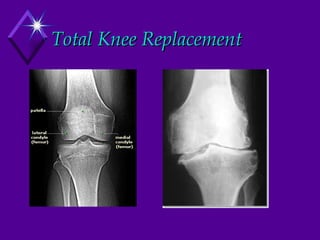

Total Knee Replacement